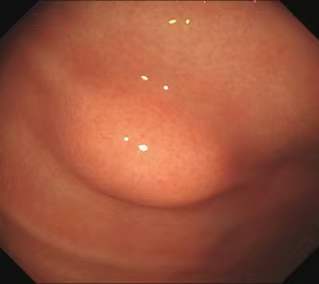

超声微探头通过钳道对病灶进行超声检查超声内镜的应用1、消化道黏膜下病变的诊断

通常消化道可以分为5层,从内到外依次为粘膜层、粘膜肌层、粘膜下层、固有肌层、浆膜层。由于胃镜和肠镜是肉眼可见光成像,只能看到消化道最表面的一层(粘膜层)。然而有些病变来源于粘膜下,此时普通胃肠镜就不能透过粘膜对粘膜下的病变做出诊断;还有些病变位于胃腔外紧贴胃壁,普通胃肠镜更是难以诊断。超声内镜将内镜和超声的功能结合在一起,能更好地对粘膜下结构或病变进行观察和判断

。

胃体粘膜下脂肪瘤